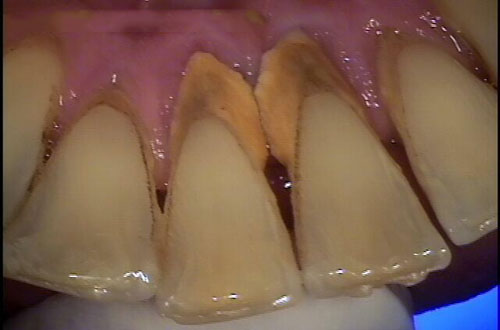

Câu hỏi: Chào bác sĩ Hoàn Mỹ. Em đã cạo vôi răng khoảng 2 tháng trước nhưng khi soi gương em vẫn thấy rất nhiều mảng bám ở cổ răng…